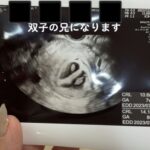

兄弟でだるまさんがころんだ(@1.and.triple_mamさんより提供)